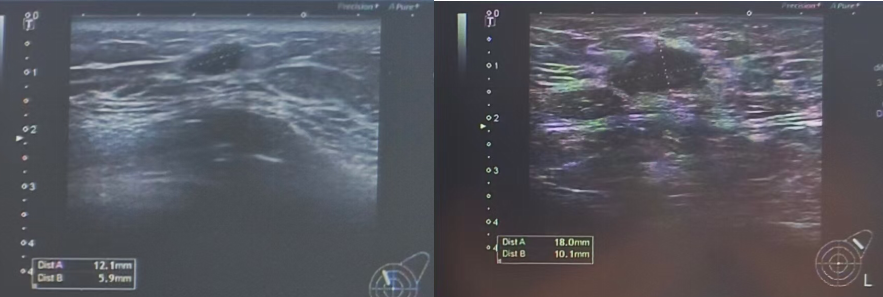

乳腺彩超(2024年05月24日 我院):

图 乳腺彩超(2024年05月24日 我院)

(左):左侧腋窝淋巴结3.93*2.40cm;(右):右侧腋窝淋巴结2.44*0.99cm

1、右侧胸壁可及低回声结节,大小约2.04*0.46cm,边界欠清,形态不规则。

2、胸骨偏右侧皮下脂肪层可及多发低回声结节,较大者约0.91*0.42cm,中间高回声,外周低回声,边界欠清,形态不规则,未见明显明显异常血流信号。

3、左乳11点距乳头2.0cm可及低回声结节,大小约1.75*0.99cm,形态规则,边界清,周边可及高回声声晕,血流信号较丰富。

4、双侧腋窝处可及多发低回声结节,右侧较大者约2.44*0.99cm,左侧较大者3.93*2.40cm,边界欠清,形态不规则。